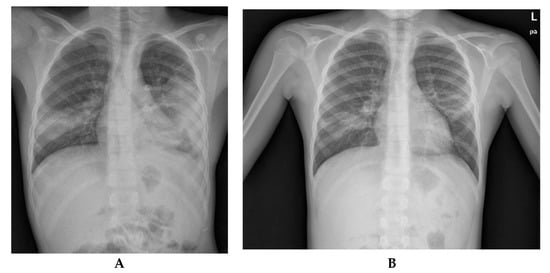

2. Case Report